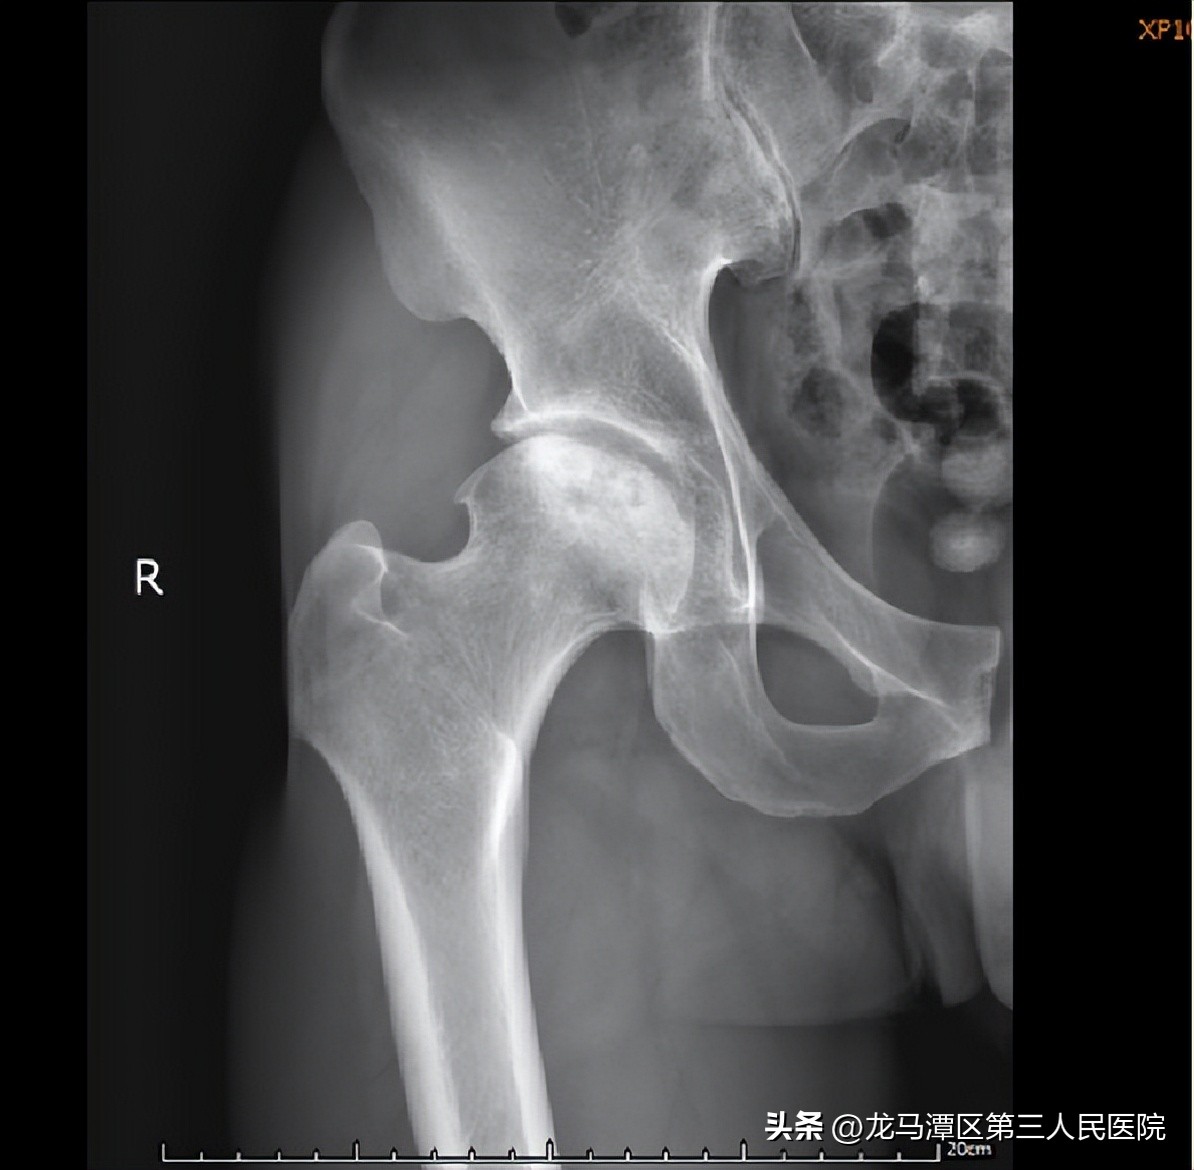

段某 男 28岁

主 诉:反复双髋关节疼痛3年余

患者于2019年01月31日因“酒精性双侧股骨头缺血性坏死”行手术治疗效果明显好转,3年回访。

股骨头缺血性坏死不单是骨质的改变,也包括股骨头软骨软化、碎裂、游离体、滑膜增生肥厚等。髋关节镜主要针对于股骨头塌陷前(Ficat 分期I~Ⅲ期)。

对于年龄较轻、早期病变和保守治疗无效的患者,早期采取小直径,低转速,多孔道不同方向的钻孔减压和髋关节镜下清理术+自体造血干细胞移植,为较理想的选择。可有助于减轻关节疼痛,改善功能,延缓病情发展。